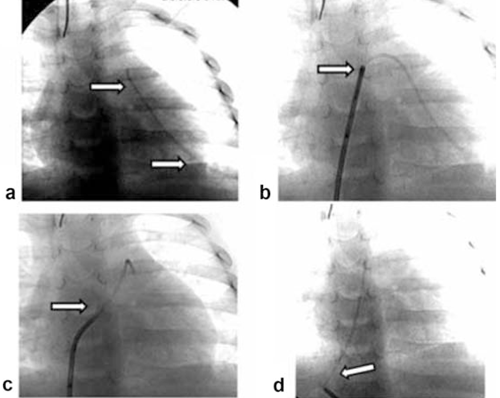

Para su captura, muchas veces es necesaria la acción de algún catéter preformado, con lo cual movilizar y colocar el cuerpo extraño en una posición más favorable para su captura con un material adecuado y su extracción posterior. Una vez localizado en una posición accesible, se dispone de diferentes catéteres con lo cual lograr su extracción definitiva, como los catéteres lazo, en cestilla y biótomo (Figura 1).

Figura 1: Diferentes formas de catéteres extractores; a, b y c: catéteres lazo, d, e y f: catéteres en cestilla.